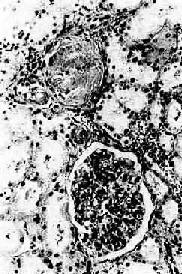

镜 检下,肾细动脉硬化明显,小叶间动脉及弓形动脉内膜增厚。依病程而有多少不等的入球动脉及肾小球发生玻璃样变(图8-12)。附近的肾小管由于缺血而萎 缩、消失,间质结缔组织增生及淋巴细胞浸润。该处由于肾实质萎缩和结缔组织收缩而形成凹陷的固缩病灶,周围健存的肾小球发生代偿性肥大,所属肾小管亦呈代 偿性扩张,使局部肾组织向表面隆起,形成肉眼所见的无数红色细颗粒(由于该处血供良好而呈红色)。

高血压病之肾

图8-12 高血压病之肾

肾小球入球小动脉管壁玻璃样变性,肾小球纤维化,玻璃样变